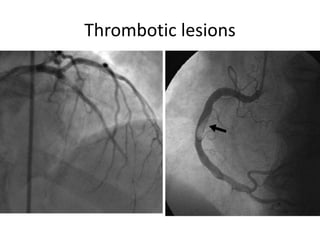

Thrombotic lesions

Left main thrombotic occlusion and

case of RCA spontaneous dissection

Left main thromboticocclusion and case of RCA spontaneous dissection